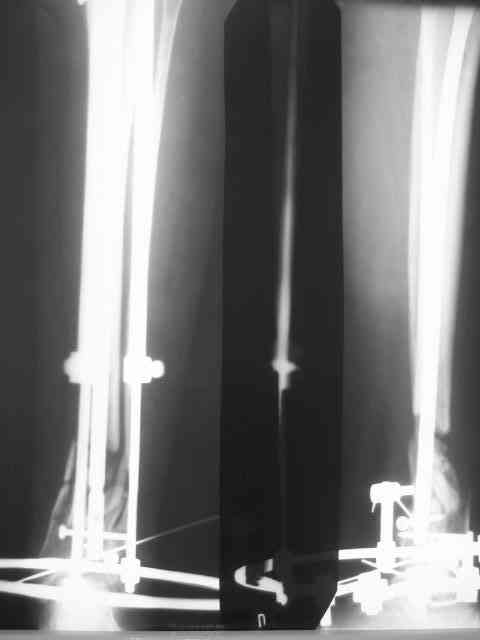

Из истории выяснилось: травма 29.01.07 Диагноз: Открытый оскольчатый перелом н/3 костей голени (якобы 2 Б Каплан), при поступлении операция из трех букв и скелетное вытяжение + остальная терапия. Затем выполнили остеосинтез штифтом (походу Эксперт стоит) видимо хотели зацепится за дистальный отломок, но скорей всего все было нестабильно и накинули этот сокращенный АВФ. На сегодня (162 дня): Больная ходит с ограниченной нагрузкой на конечность (трость). Движения в г/стопе качательные. Трофика мягких тканей не настораживает. Воспаления м/тканей нет.В планах: 1. удаление штифта 2.Наложение стандартного АВФ с фиксацией стопы и устранение всех смещений 3.Резекция нежизнеспособных костных отломков 4.Остеотомия в/3 большеберцовой кости с последующей дистракцией и замещением дефекта.Хотелось бы выслушать мнение по этому случаю!Возможен ли вариант если на опер.столе удастся устранить смещения одномоментной репозицией АВФ и не удалять штифт а производить транспорт большеберцовой кости на штифте? И стоит ли при таком коротком дистальном отломке пытаться блокировать в низу (имеется в виду в АВФ)Спасибо.

Уважаемый коллега, на счет того,что надо интрамедулярный штифт надо убрать, это однозначно, так как большой диастаз между отломками,перелом не срастется, а АПФ фиксировать дистальный отломок очень трудно и будет нестабильность,я бы сделал мостовидный остеосинтез метафизарной пластиной с блокированием, с декортикацией и замещением дефекта аутокостью или другими трансплантатами, и соотвественно остеотомия малоберцовой кости в с/3 или в/3

Уважаемые коллеги, предлагаю в данной ситуации провести динамизацию: удалить лишь дистальный блокирующий винт и снять напряжение на стержнях АВФ, что должно стимулировать явление консолидации.

Приветсвую, коллега! Думаю, будет более разумная такая тактика: 1.Удаление стержня. 2. Адаптационная резекция места перелома. 3. Дистракционный остеосинтез с остеотомией в проксимальном метафизе костей голени с целью дозированного восстановления длины конечности.